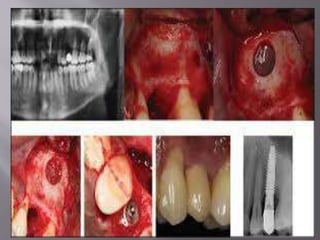

 Socket Preservation:

The alveolar bone uneventfully resorbs after extraction and results in residual ridge

morphology with compromised horizontal and vertical bone volume to receive implant

and a lingually positioned crest due to greater resorption on the buccal aspect.[Socket

grafting at the time of extraction is a preventive procedure, which does not inhibit the

resorption but limits it.Moreover, the minimal amount of resorption after socket

grafting happens in a predictable fashion. Also, the magnitude of volume loss is less in

the grafted socket versus the naive socket. This has been substantiated by a recent meta-

analysis where ≈1.4 mm lesser horizontal bone loss and ≈1.8 mm lesser vertical bone

loss were reported in grafted sites compared to nongrafted sites. However, it is

interesting to note that similar mean implant survival rates has been reported for

implants placed in preserved sites versus naive sites. Additionally, the bone grafting

may still be needed at the time of implant placement as it is only possible to limit the

alveolar bone resorption and yet not possible to completely eliminate it.These facts

question the rationale of socket preservation. In the light of these facts, it is

recommended that it should be performed in aesthetic areas in case of buccal bone

thickness≤2 mm or when there is a proximity to anatomic structures, i.e., maxillary

sinus or mandibular canal. Also, overaugmentation may help, especially in aesthetically

sensitive areas where the buccal bone contour is critical